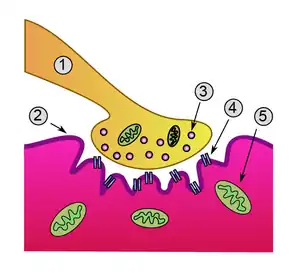

Neuromuscular junction: 1. Axon 2. Muscle cell membrane 3. Synaptic vesicle 4. Nicotinic acetylcholine receptor 5. Mitochondrion

Neuromuscular junction: 1. Axon 2. Muscle cell membrane 3. Synaptic vesicle 4. Nicotinic acetylcholine receptor 5. Mitochondrion -

Myasthenia gravis is an autoimmune disease which results from antibodies that block or destroy nicotinic acetylcholine receptors at the junction between the nerve and muscle.[1] This prevents nerve impulses from triggering muscle contractions.[1] Some medicines may worsen the weakness.[5] Rarely, an inherited genetic defect in the neuromuscular junction results in a similar condition known as congenital myasthenia.[6][7] Babies of mothers with myasthenia may have symptoms during their first few months of life, known as neonatal myasthenia.[1] Diagnosis can be supported by blood tests for specific antibodies, the edrophonium test, or a nerve conduction study.[1]

MG is an autoimmune synaptopathy. The disorder occurs when the immune system malfunctions and generates antibodies that attack the body's tissues. The antibodies in MG attack a normal human protein, the nicotinic acetylcholine receptor, or a related protein called MuSK a muscle-specific kinase.[19] Other less frequent antibodies are found against LRP4, Agrin and titin proteins.[20][21]